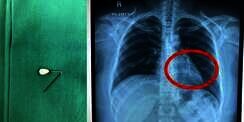

Tertelan Saat Pakai Jilbab, Jarum Pentul Nyangkut di Paru-paru